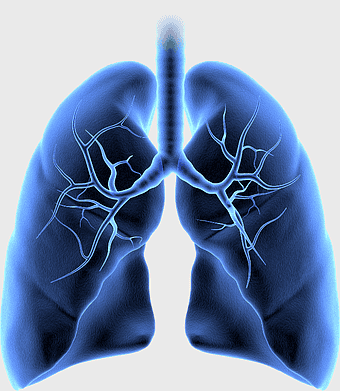

Pulmonary edema symptoms, chronic obstructive pulmonary disease diagram, kidney failure effects on lungs, pulmonary circulation illustration, lung disease diagnostic, respiratory health visuals, human anatomy respiratory system, PNG

- pulmonary edema symptoms

- chronic obstructive pulmonary disease diagram

- pulmonary circulation illustration

- lung disease diagnostic

- respiratory health visuals

- human anatomy respiratory system

lungs illustration, respiratory system diagram, idiopathic pulmonary fibrosis, breathing anatomy, pulmonary health, respiratory tract function, lung disease awareness -

lungs illustration, respiratory system diagram, human lungs anatomy, pulmonary alveolus structure, bronchial tree visualization, trachea and bronchi, lung lobes detail -

Respiratory system anatomy, human breathing process, pulmonary alveoli structure, respiratory therapist training, respiratory health education, lung function diagram, respiratory disease prevention -

human lung anatomy, respiratory system illustration, heart and lungs diagram, bronchus structure, pulmonary function, thoracic cavity, medical imaging analysis -

lung organ, small lungs, respiratory system, pink trachea, human anatomy, medical illustration, pulmonary health -

human intestine illustration, Pulmonary alveolus Anatomy, Alveolar venous blood vessels, Bronchiole, respiratory system diagram, pulmonary circulation, lung vascular structure -

lung cancer metastasis, human lung anatomy, pulmonary carcinoma cells, prognosis of lung cancer, respiratory disease illustration, medical oncology, thoracic organ health -

Lung Pulmonary circulation, Bronchus Disease, Heart anatomy, respiratory system diagram, cardiovascular health, medical illustration, pulmonary function test -

Lung Respiratory system, trachea and bronchus, pink lungs illustration, breathing anatomy, pulmonary health, respiratory function, medical education visuals -

human lungs illustration, respiratory system anatomy, carina of trachea, blood vessel in lungs, pulmonary function, respiratory tract diagram, bronchial tree structure -

Respiratory system diagram, bronchiole structure, lung anatomy illustration, pulmonary alveolus function, respiratory health, breathing process visualization, trachea pathway -

lung anatomy, respiratory system illustration, pulmonary alveoli structure, trachea and bronchi, human lung function, diaphragm movement, breathing process diagram -

Human Respiratory System illustration, pulmonary anatomy, trachea structure, respiratory organ function, bronchial tree, alveoli exchange, thoracic cavity -